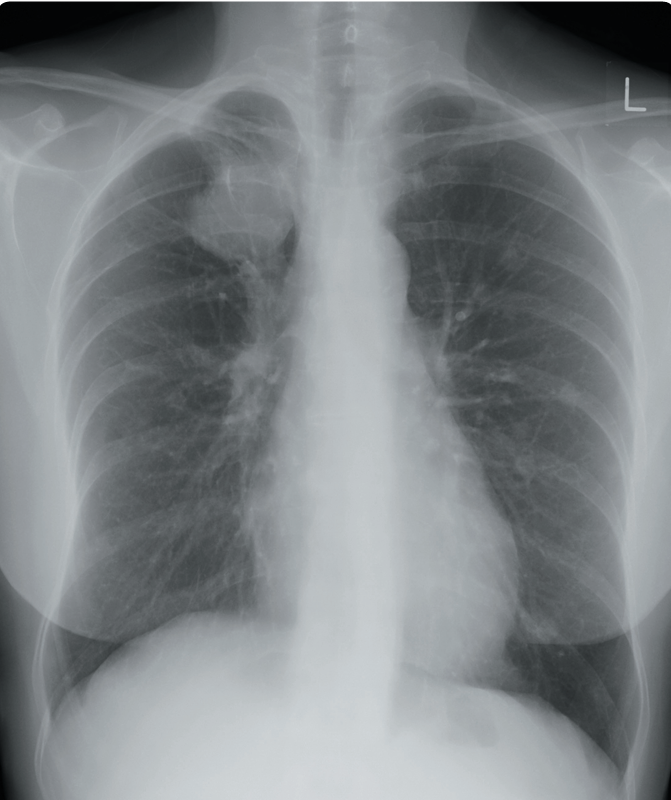

Un hombre de 55 años se presenta a la sala de emergencias con un historial de 2 semanas de tos productiva y dificultad para respirar. Tiene antecedentes de reflujo gastroesofágico. No es fumador. En el examen físico, presenta saturaciones del 100% en aire y no tiene fiebre. Los pulmones son resonantes en toda su extensión, con buena entrada de aire bilateralmente. Se solicita una radiografía de tórax para evaluar posible neumonía, derrame o colapso.

La radiografía muestra una opacidad retrocardíaca con un nivel aire-líquido, consistente con una hernia de hiato de tamaño moderado. Los pulmones están claros.

Se puede requerir tratamiento si la enfermedad por reflujo gastroesofágico es sintomática; de lo contrario, no es necesario tratamiento para la hernia de hiato.